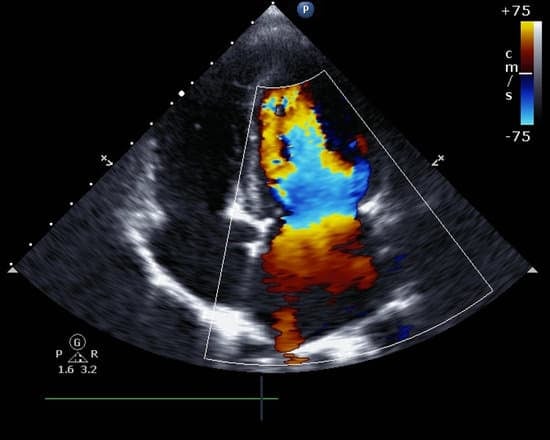

혈류 속도와 방향: 도플러 초음파를 이용해 심장 내 혈류의 속도와 방향을 평가합니다. 이는 심장 내 압력 차이를 측정하는 데 유용합니다.